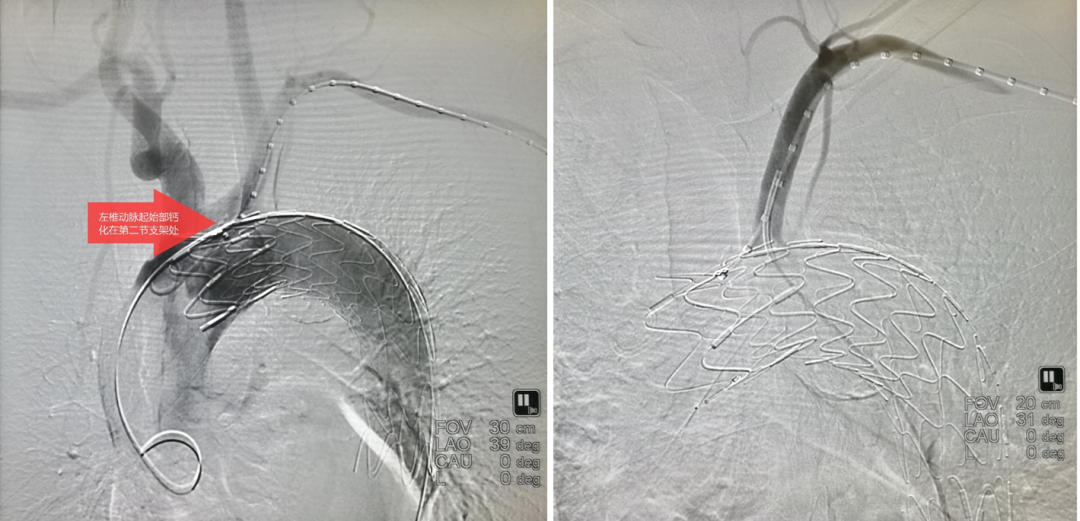

基于上述分析,我们于2019年申请发明专利,并联合企业开发出原型样机。其核心创新在于:“避分支、稳锚定、垂穿透”。

破膜装置

具体操作分两种模式:

预置模式:

先将器械送入主动脉,在目标分支开口处预张开前盘;

轻微回拉,使盘片卡住分支开口边缘;

再释放主体覆膜支架;

最后通过内置破膜针垂直穿透覆膜支架,完成开窗。

在主动脉内张开,轻轻牵张,使其卡在分支开口

后顶模式:

先释放主体覆膜支架;

将长鞘顶住支架,推送器械使其前盘在主动脉内张开并向后牵拉,同样实现锚定于分支开口;

再行破膜。

输送器顶住覆膜支架,张开后向后牵拉卡住分支开口